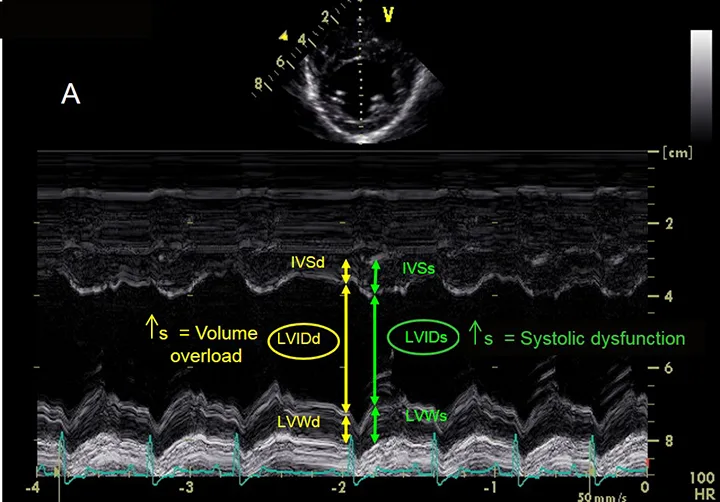

Ultrasound image with labels demonstrating measurement of the aorta in yellow and the left atrium in green.

FIGURE 3B

Assessment of left atrial size. This image demonstrates the measurement of the aorta (yellow arrow) and left atrium (green arrow).

• Image seen: In the view shown in this figure, the ratio of the left atrium (LA) to the aorta (Ao) should be <1.5:1 (also see Figure 3B).1

Assessing Left Atrial Size

To assess the size of the left atrium, the transverse diameters of the aorta and left atrium are measured in the right sided short-axis view. Of note, other views can be used to obtain measurements, but these are the author’s preferred views. Measurements are taken in early ventricular diastole using the first frame after aortic ejection, where the Ao appears as a symmetric three-leaf clover with closed aortic valves and a teardrop-shaped LA.

1. To measure Ao, the first caliper is placed at the midpoint of the convex curvature of the wall of the right aortic sinus. The caliper cross is positioned as close as possible to the blood-tissue interface.

2. The second caliper is positioned at the point where the aortic wall and the noncoronary and left coronary aortic cusps merge. This measurement point is defined by a slight increase in echogenicity where the three structures merge.

3. The LA is measured from this point by extending the Ao line to the blood-tissue interface of the LA wall.

4. If a pulmonary vein enters the LA at the desired measurement point, the caliper is placed either on an extrapolation of the atrial border or immediately medial or lateral to the vein.2